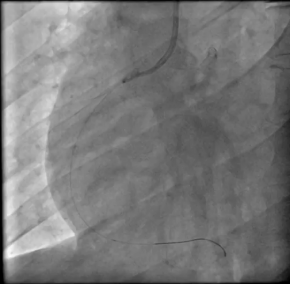

冠脉造影提示严重三支病变:

image.png

LAD急性闭塞

LCX(左)RCA(右)慢性闭塞

治疗策略:大剂量血管活性药物+IABP循环支持,建立PCI通道、急诊处理LAD。